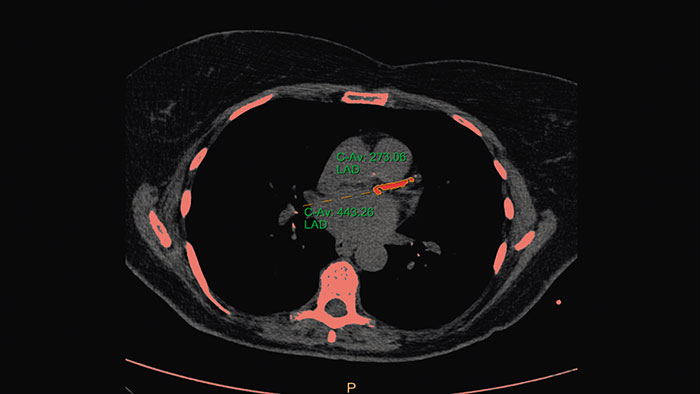

Calcium Scoring

CT Calcium Scoring

One-click 3D calcium segmentation

One-click 3D segmentation and quantification for coronary arteries calcifications including mass, Agatston, and volume scores.

• Calcium scoring is achieved by performing automatic calculations on CT HU values in user-defined regions of interest.

• Supports ECG-gated and non ECG-gated images in DICOM format from Philips and other vendors (mass score can only be calculated for Philips CT scanners).

• The application incorporates parameters from the MESA (Multi Ethnic Study of Atherosclerosis) database.